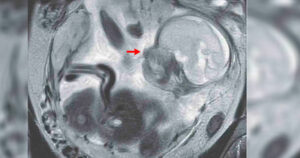

Mujer con calambres estomacales descubre que un bebé se desarrollaba en su intestino.